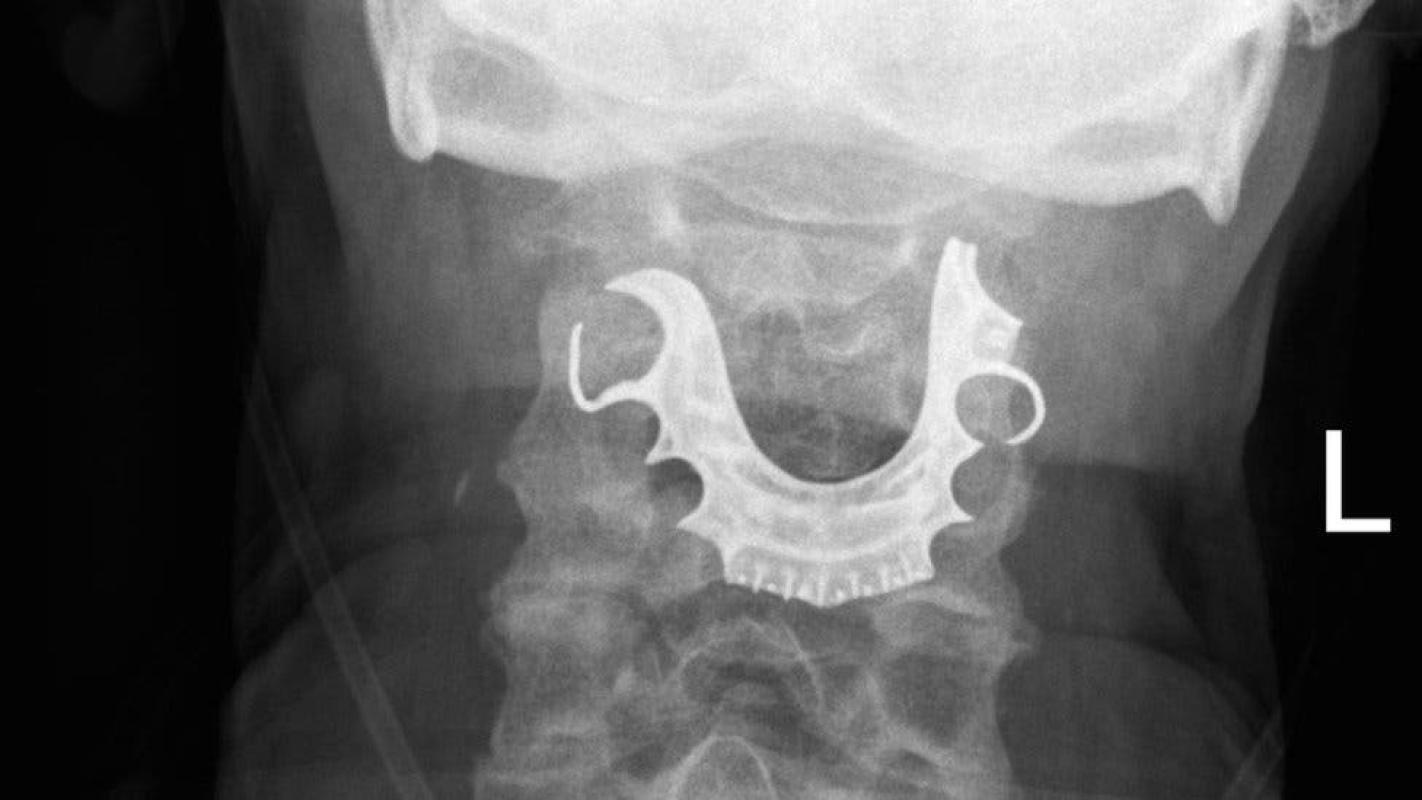

Cuando el hombre regresó nuevamente dos días después, los médicos revisaron su garganta y fue entonces que encontraron un objeto semicircular sobre sus cuerdas vocales.

Y todo empezó a cobrar sentido cuando el hombre les contó que había perdido su dentadura postiza durante su operación.

Una vez que que le hallaron el objeto en la laringe, ocho días después de la primera operación, el paciente tuvo que ser intervenido nuevamente para remover la dentadura postiza de su cuerpo.